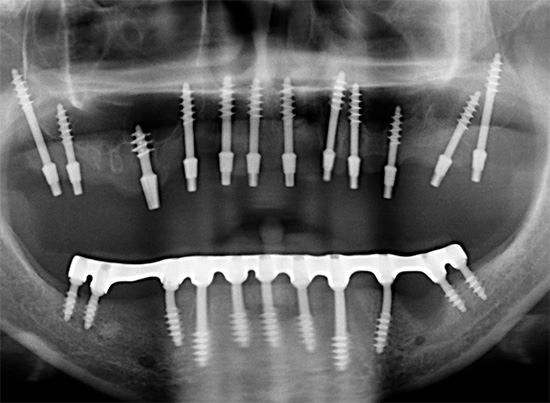

Deve-se ter em mente que o conceito de "implantação basal", como tal, hoje é coisa do passado. Existe um protocolo de carregamento imediato, que inclui várias tecnologias para restauração dentária, dependendo do quadro clínico. É adequado para restaurações simples e múltiplas, incluindo a ausência completa de dentes - um exemplo correspondente é mostrado nas fotografias abaixo:

O protocolo de carregamento imediato implica a realização da operação em uma única etapa, bem como o carregamento instantâneo (imediato) da prótese - daí o nome (implantação de dentes com carga imediata, implantação em estágio único, sinônimos simultâneos e outros).

Esse protocolo também é usado para restaurações únicas, mas é mais adequado para pacientes com desdentamento completo ou falta de segmentos de dentes inteiros. Além disso, nos casos em que são observados processos atróficos no tecido da mandíbula, a técnica também pode ser aplicada através do uso de partes fortes e estéreis do osso (falaremos mais sobre isso mais adiante).

Entre as tecnologias de carregamento imediato, vários protocolos principais podem ser distinguidos: próteses em quatro implantes (all-on-4 - patenteados pela Nobel), em seis implantes (all-on-6) e o próprio método basal.

Em todos os casos, são utilizados implantes instalados precisamente nas camadas profundas do tecido ósseo (existem muitos modelos e variedades desses implantes). Eles estão ligados não apenas na zona alveolar, mas também na seção basal, a membrana cortical do osso. E com atrofia aguda, os ossos e contrafortes zigomáticos (linhas de força) do crânio também são usados. O grau de fixação de tais implantes é várias vezes maior e atinge 100 Newtons versus implantes clássicos, com um índice de 30 a 45 Newtons.